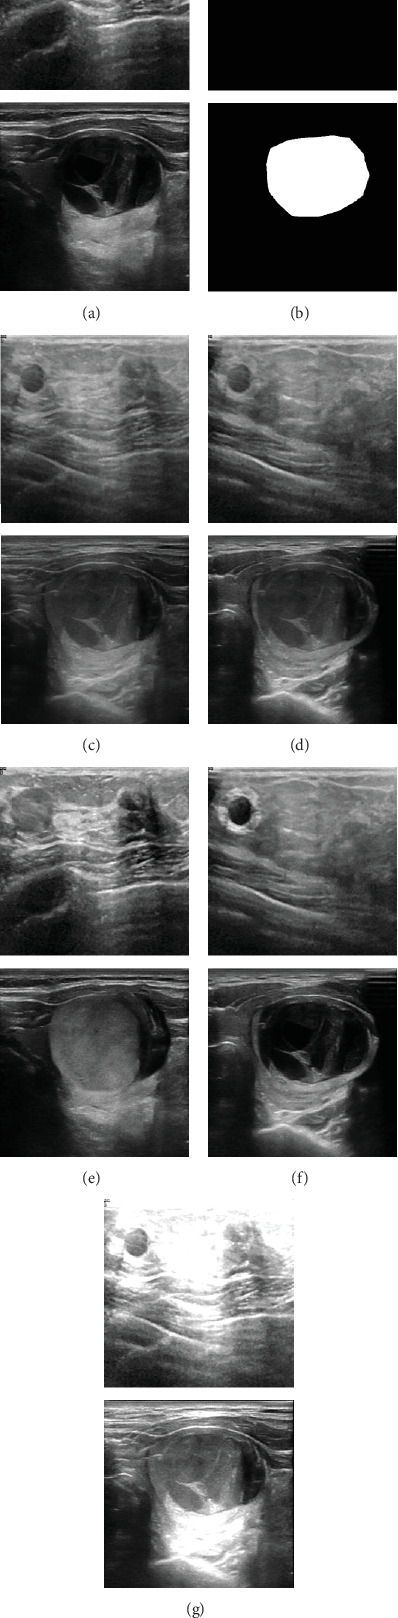

Automated lesion segmentation in ultrasound (US) images based on deep learning (DL) approaches plays a crucial role in disease diagnosis and treatment. However, the successful implementation of these approaches is conditioned by large-scale and diverse annotated datasets whose obtention is tedious and expertise demanding. Although methods like generative adversarial networks (GANs) can help address sample scarcity, they are often associated with complex training processes and high computational demands, which can limit their practicality and feasibility, especially in resource-constrained scenarios. Therefore, this study is aimed at exploring new solutions to address the challenge of limited annotated samples in automated lesion delineation in US images. Specifically, we propose five distinct mixed sample augmentation strategies and assess their effectiveness using four deep segmentation models for the delineation of two lesion types: breast and thyroid lesions. Extensive experimental analyses indicate that the effectiveness of these augmentation strategies is strongly influenced by both the lesion type and the model architecture. When appropriately selected, these strategies result in substantial performance improvements, with the Dice and Jaccard indices increasing by up to 37.95% and 36.32% for breast lesions and 14.59% and 13.01% for thyroid lesions, respectively. These improvements highlight the potential of the proposed strategies as a reliable solution to address data scarcity in automated lesion segmentation tasks. Furthermore, the study emphasizes the critical importance of carefully selecting data augmentation approaches, offering valuable insights into how their strategic application can significantly enhance the performance of DL models.

Abstract Image